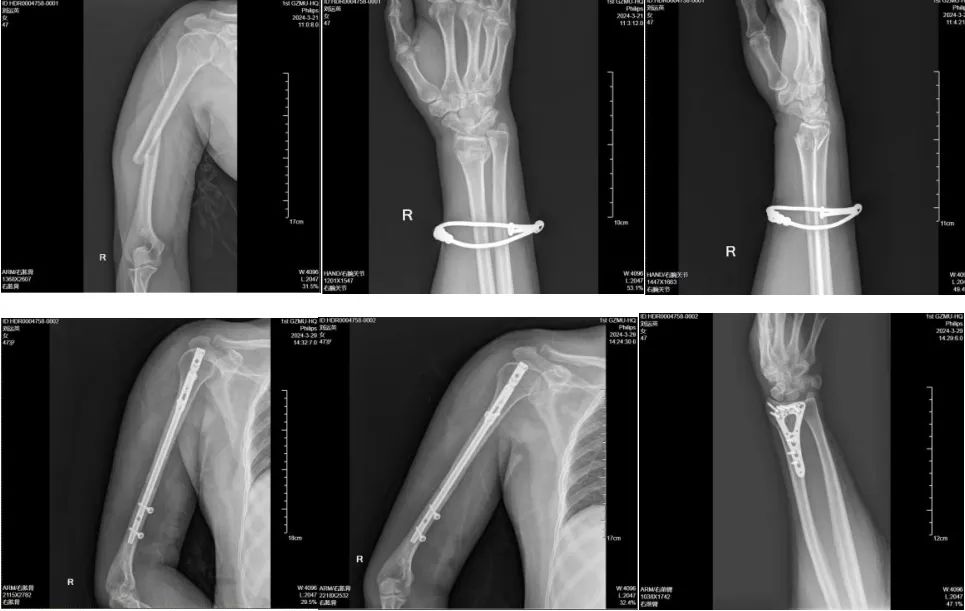

01肱骨骨折+桡骨远端骨折

47岁的刘女士(化名),今年在工作时右臂意外遭到重击受伤,拍片发现右肱骨、桡骨远端骨折,严重影响工作和生活,来到广医一院横琴医院就诊。 在广医一院横琴医院骨科副主任医师闫伦春门诊就诊发现其右肱骨骨折、右桡骨远端骨折,闫伦春副主任医师团队为其行“右肱骨骨折闭合复位髓内钉内固定术+右桡骨远端骨折切开复位钢板螺钉内固定术”。术后进行逐步开始功能锻炼,现已完全康复。 02 股骨骨折 股骨是人体最长的骨骼,支撑着整个身体的重量。股骨骨折多见于老年人,常因跌倒等意外发生,严重时可危及生命。 50多岁的公司职员王先生(化名),车祸致右大腿疼痛,活动受限,无法站立、行走,检查发现其右侧股骨颈、股骨干粉碎性骨折,闫伦春副主任医师骨科手术团队为其行“右股骨骨折闭合复位髓内针内固定术,良好的复位和稳定的固定,早期的功能锻炼,伤后3个月后,王先生康复非常满意,没有遗留功能障碍。 03 胫骨骨折 胫腓骨骨干骨折在全身骨折中最为常见,常因车祸、外伤等意外发生,严重时可导致功能障碍甚至截肢的灾难后遗症。 35岁游先生意外致左小腿疼痛,活动受限,不能站立、行走,求治住院,检查发现胫骨骨折,沟通后给予“闭合复位胫骨髓内钉内定治疗”,手术顺利,术后第二天患者下地行走,顺利康复。 治疗亮点 广医一院横琴医院骨科团队日常工作的部分病例展示,在该类骨科损伤的治疗方面积累了大量临床案例和丰富经验,这些手术的亮点是: ➤ 精准复位:采用微创技术,减少手术创伤,确保骨折端精确复位; ➤ 坚强固定:骨折复位的同时,对骨折端进行可靠的固定; ➤ 早期康复:康复科帮助患者早期进行功能锻炼,加速康复进程。 随着医学进步,骨科手术治疗能帮助患者更快更好地恢复运动功能,也能让创口更加美观,那么,骨折发生后应该注意哪些问题。 骨折后如何应急处理? 当发生骨折时,正确的应急处理至关重要。以下是几个关键步骤: ➤ 保持冷静,立即停止活动:避免骨折部位进一步损伤。 ➤ 固定骨折部位:使用身边的物品对骨折部位进行临时固定,减少移动和疼痛。 ➤ 冷敷缓解疼痛:用冰块或冷湿毛巾冷敷,减轻肿胀和疼痛。 ➤ 及时就医:尽快就医,由专业医生进行评估和治疗。 骨折可以保守治疗吗? 骨折是否需要手术取决于骨折的类型、移位程度以及患者的身体状况。一般来说,闭合性骨折且移位不明显时,可以通过保守治疗(如石膏固定)促进愈合;而开放性骨折、粉碎性骨折或移位明显的骨折,则可能需要手术治疗以达到解剖复位和稳定固定。 骨折多久能愈合? 骨折的愈合时间因个体差异而异,一般成人骨折需要3个月到半年左右的时间。但具体时间还取决于骨折的部位、类型、治疗方法以及患者的年龄、营养状况等因素。在愈合过程中,患者应遵循医生的建议进行康复训练,以促进骨折部位的功能恢复。